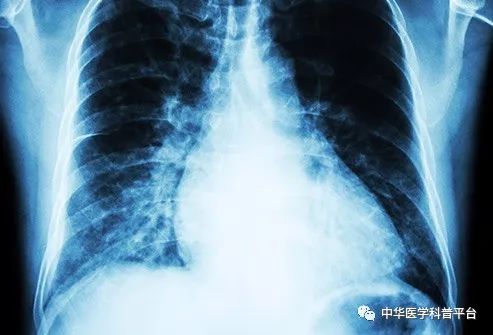

高血压是一种常见病和多发病,它所带来的危害有很多,今天就来介绍一下高血压所引起的各种疾病。

中风:高血压是中风的首要风险,中风一般分为两种类型:出血性和缺血性,出血性是指大脑中的动脉破裂,而缺血性是指斑块积聚或破裂,阻止了血液流向脑组织。如果你出现了脸部不对称,手臂无力或言语不利等症状,记得及时就医。